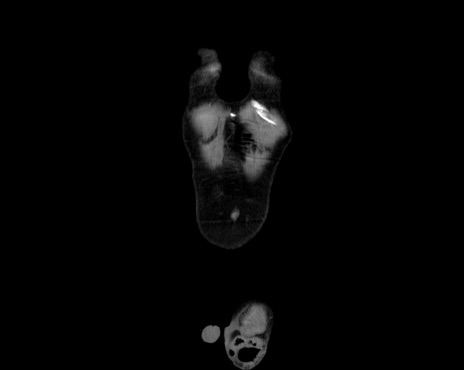

横断像